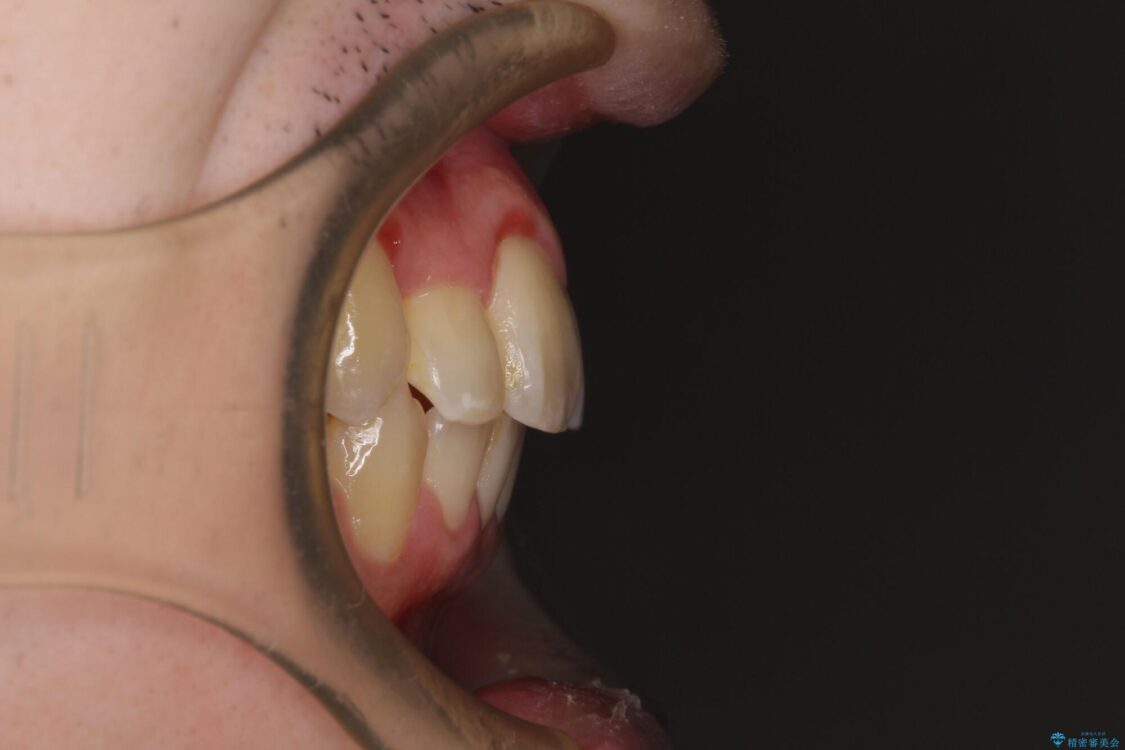

八重歯や奥歯の噛みにくさを気にして来院された患者様です。

前歯のクロスバイトや八重歯の他に、左右最後臼歯のシザーズバイト(鋏状咬合)が認められました。

治療前

• 全顎的なクロスバイト 補助装置を用いてワイヤー矯正 治療前画像